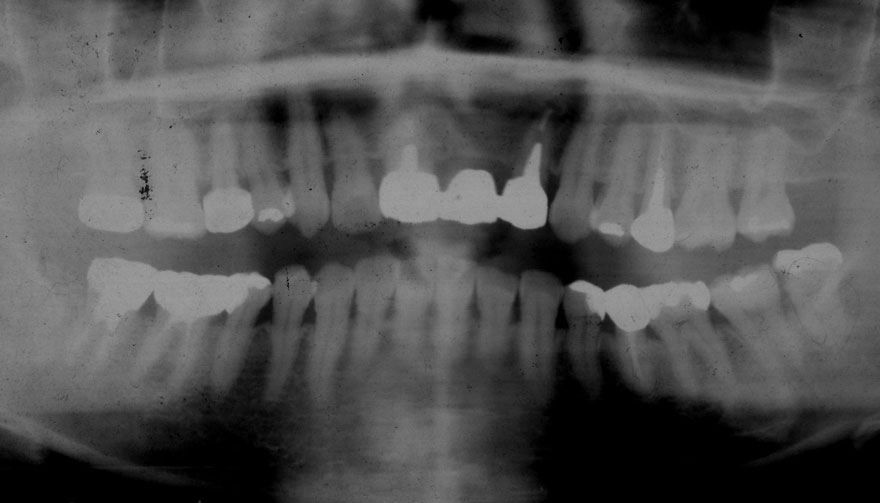

初診時 36歳 女性 平均歯槽骨喪失量:2.70mm

30年後 66歳

平均歯槽骨喪失量:3.26mm

30年間喪失量:-0.55mm

年間喪失速度:-0.018mm

(ケア頻度:3.01ヵ月ごと)